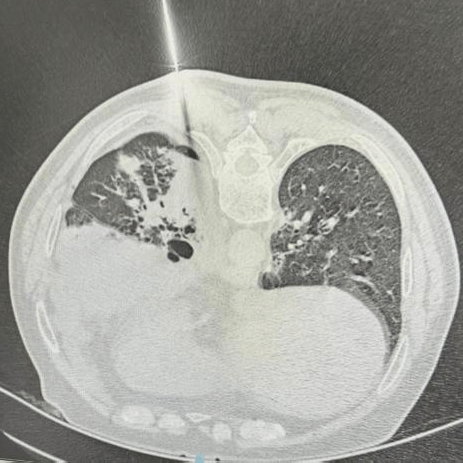

运用先进的检查技术如超薄层螺旋CT、PET-CT、肺部超声、CT引导下肺部小结节精准穿刺、快速病理诊断技术,每年对上千例肺部结节疾病患者进行精准诊断,并给予合理治疗。

CT引导下肺结节穿刺治疗